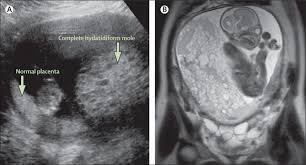

Ultrasound remains the radiological investigation of choice for initial.

The latter four entities are referred to as gestational trophoblastic neoplasia GTN. A common characteristic of all gestational trophoblastic disease is an abnormal proliferation of trophoblast but different components predominate in different tumors. Ultrasound remains the radiological investigation of choice for initial. Gestational trophoblastic neoplasia GTN encompasses a broad spectrum of placental lesions from the pre-malignant hydatidiform mole complete and partial through to the malignant invasive mole choriocarcinoma and rare placental site trophoblastic tumour PSTT. The latter four entities are referred to as gestational trophoblastic neoplasia GTN. There are several histologically distinct types of GTD that range from premalignant complete and partial hydatidiform moles HMs to malignant diseases also known as gestational trophoblastic. Ultrasound in the Diagnosis and Management of GTN Gestational trophoblastic neoplasia GTN includes invasive mole choriocarcinoma PSTT and ETT. Because it is an unusual and serious disease that affects women of reproductive age as well as because its appropriate treatment results in high cure rates it is crucial that radiologists be familiar with gestational trophoblastic disease in order to facilitate its early diagnosis and to ensure appropriate follow-up imaging. Gestational trophoblastic disease GTD is a spectrum of both benign and malignant gestational tumors including hydatidiform mole complete and partial invasive mole Choriocarcinoma placental site trophoblastic tumor and epithelioid trophoblastic tumor.

Gestational trophoblastic disease GTD encompasses a heterogeneous group of lesions including hydatidiform mole invasive mole choriocarcinoma and placental site trophoblastic tumor Mazur and Kurman 1994. The term gestational trophoblastic disease GTD encompasses a spectrum of tumors with a wide range of biologic behavior and potential for distant metastases. Gestational trophoblastic disease GTD is a term used for a group of pregnancy-related tumours. GTD refers to both the benign and malignant entities in the spectrum and includes hydatidiform mole complete and partial invasive mole choriocarcinoma placental site trophoblastic tumor PSTT and epithelioid trophoblastic tumor ETT. There are several histologically distinct types of GTD that range from premalignant complete and partial hydatidiform moles HMs to malignant diseases also known as gestational trophoblastic. Ultrasound in the Diagnosis and Management of GTN Gestational trophoblastic neoplasia GTN includes invasive mole choriocarcinoma PSTT and ETT. GTD refers to both the benign and malignant entities in the spectrum and includes hydatidiform mole complete and partial invasive mole choriocarcinoma placental.